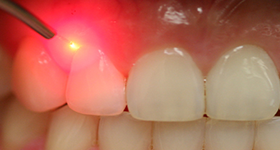

Painless dentistry has entered a new era with Lasers. An amplified high energy light source replaces the dental drill and scalpel which patients have feared for many years. At Amrapali Dental Clinic, we use Dental lasers for the following applications:

As patients typically feel less pain with Lasers when compared to the drill, little or no anesthesia is needed when a laser is used. If you hate the sound of the dental drill, you will love the laser.

The use of the Dental laser depends on your clinical situation, and your eligibility for its use will be determined at the time of treatment planning.